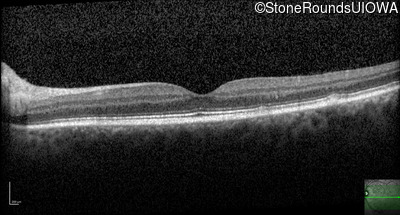

AR Stargardt Disease (IIA)

Age at visit: 30 years

This 30 year old asymptomatic man had fundus abnormalities identified incidentally on a routine exam.

Diagnosis & molecular findings

Disease Gene Allele 1 variant(s) Allele 2 variant(s) Inheritance mode

AR Stargardt Disease ABCA4 IVS30+1321 A>G Asn965Ser AAT>AGT AR